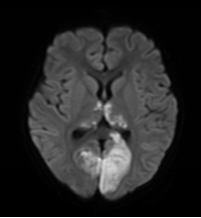

答:確診主要依靠頭顱磁共振檢查。引起兒童腦梗死的原因多樣,某些原因還會誘發(fā)腦梗死的復(fù)發(fā),因此對于腦梗死的患兒需進(jìn)一步評估有無心臟、血管及血液系統(tǒng)的其他危險因素。